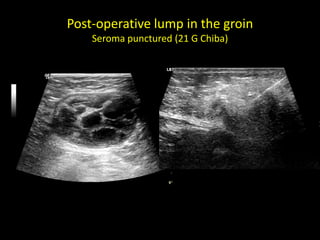

Post-operative lump in the groin

Seroma punctured (21 G Chiba)

Post-operative lump inthe groin Seroma punctured (21 G Chiba)